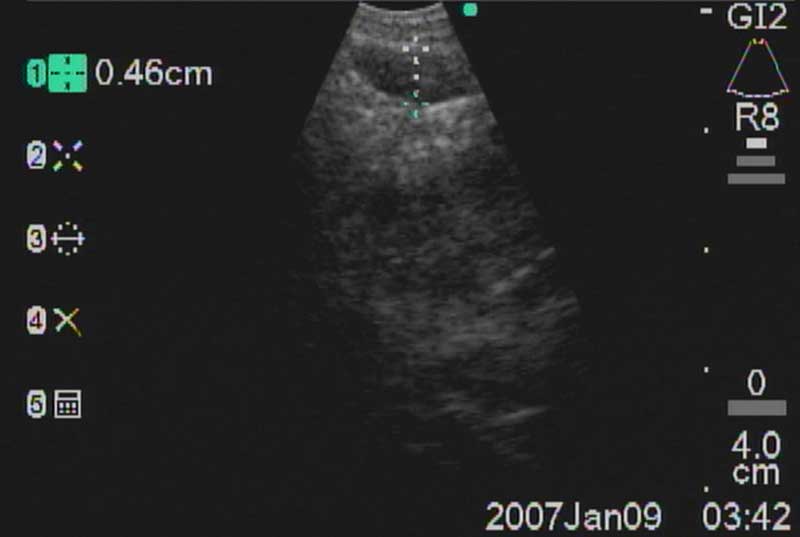

The easiest place to start ultrasound imaging is generally the right main bronchus and subcarinal areas. Pass the scope to the right side of the carina with the probe facing anteriorly and apply to the anterior wall of the RMB. This will bring into view the right main pulmonary artery. Vascular structures appear hypoechoic and pulsatile, and are usually readily discernable without using the color Doppler. If doubt persists flow within can be confirmed by switching to the Doppler overlay (B/CPD; Figures 5 and 6). Turn the scope 90 degrees counter-clockwise. This allows visualization of the subcarinal area from the right side. By moving the scope in and out the level 7 subcarinal node can usually be identified. If not, repeat this procedure in the LMB turning the scope 90 degrees clockwise instead. Once the subcarinal nodes are visualized it is relatively easy to identify other landmarks, by correlating anatomical location with the ultrasound image. It is useful to attempt to map out all nodes that you wish to biopsy first, before needle tract bleeding confounds the fiber optic image. The size of the node can be measured by freezing the US image [Freeze] and using the [Measure/Select] button and cursor scroll ball (Figures 5 and 7).

Mountain-Dresler nodal stations accessible by EBUS include stations 1,2,3,4,7,10, and 11 and lymph nodes with short axis dimensions of 5mm or greater may usually be biopsied without difficulty. Sensitivity and yield are maximized after 3 separate passes through each node. It is important to have real-time cytologic analysis and feedback in order to confirm that an adequate specimen containing lymphocytes has been achieved, which provides evidence of nodal sampling (Figure 11).